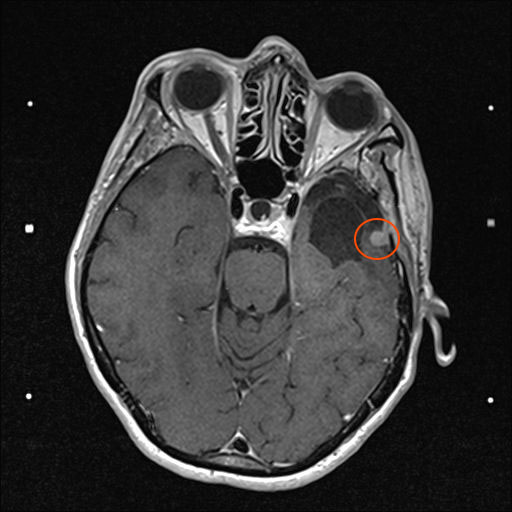

Am 03. November war mein Kontrollbesuch beim MRT. Leider ist ein kleiner Befund aufgetaucht. Schau das Video, dann kannst Du sehen.

Nun kann sich zeigen, ob die menschliche Medizin eine Lösung für mich hat. Möglichkeiten gibt es. Sogar mindestens eine, die der Neurochirurg als fein und elegant beschreibt. Gamma-Knife, eine Strahlentherapie. Klingt etwas nach Star Wars – man wird sehen, etwas abwarten ist auch drin.

2. November 2021: Leider etwas gewachsen

Heute war ich im MRT im Bremen. Der Befund des auswertenden Arztes ist, dass er der Meinung ist, dass der Tumor etwas gewachsen ist. Ich habe mir die Bilder angesehen und versucht diese Aussage zu verstehen. Vermutlich ist sie richtig, aber das Wachstum ist nicht heftig nur vielleicht von 0,7 cm auf 0,8 cm. Aber Gamma-Knife hat es offensichtlich nicht entfernt.

In der nächsten Woche gehe ich mit denm Bildmaterial zum Neurochirurgen und der wird bei der Auswertung und der daraus folgenden notwendigen Konsequenzen sicher einen Rat haben. Solange muss ich mal abwarten.